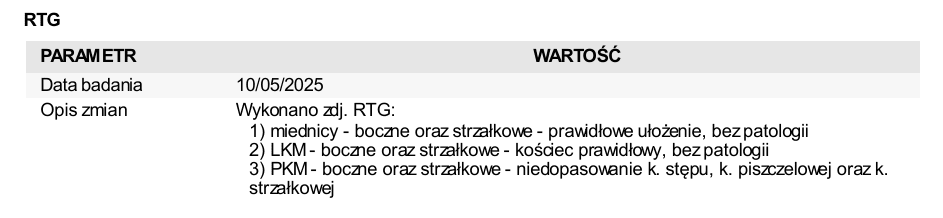

Wykonaliśmy malutkiej badania krwi, testy FIV/FELV. Koteczka ma trochę podwyższone leukocyty. Będziemy monitorować ten parametr.

Niestety problem z nóżką okazał się być o wiele bardziej poważny, niż "tylko" złamanie :-(.

Na najbliższy piątek, tj. 16 maja koteczka ma umówiony zabieg artrodezy,

Artrodeza jest zabiegiem operacyjnym trwale znoszącym ruchomość stawu. Artrodeza polega na usunięciu powierzchni stawowych i resekcji tkanki kostnej, a następnie stabilnemu zespoleniu kości tak, aby uległy trwałemu zrośnięciu.

- opłacenie pierwszej wizyty Wojtusi u weta (w tym badanie krwi, testy FIV/FELV, zdjęcia RTG w sedacji - około 600 zł